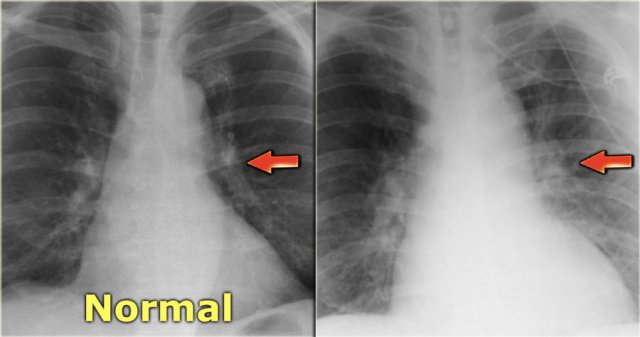

Normally the vessels in the upper lobes are smaller than the accompanying bronchus with a ratio of 0.85 (3).

At the level of the hilum they are equal and in the lower lobes the arteries are larger with a ratio of 1.35.

When there is redistribution of pulmonary blood flow there will be an increased artery-to-bronchus ratio in the upper and middle lobes.

This is best visible in the perihilar region.

On the left a patient with cardiomegaly and redistribution.

The upper lobe vessels have a diameter > 3 mm (normal 1-2 mm).

Notice the increased artery-to-bronchus ratio at hilar level (arrows).